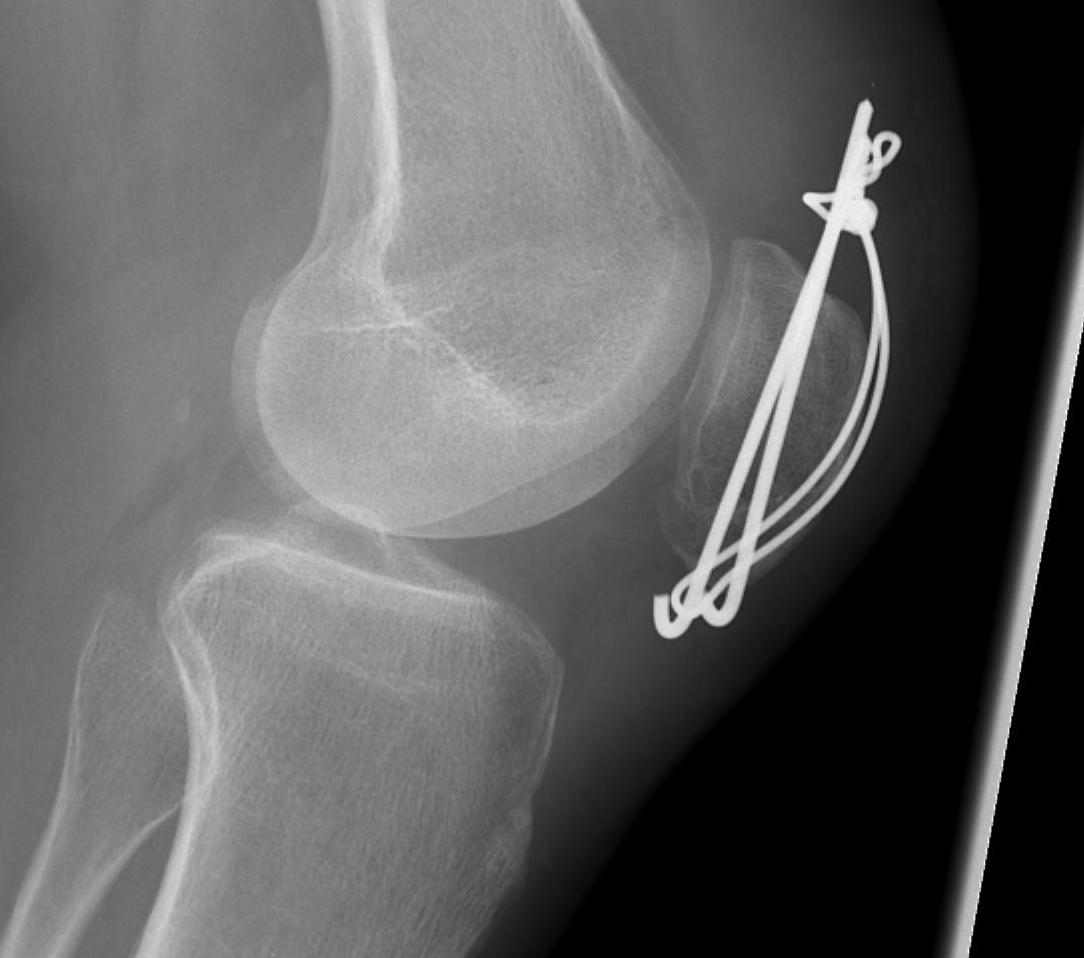

1. TBW

Technique

Concept

Excise patella in full close retinaculum tightly with VMO advancement